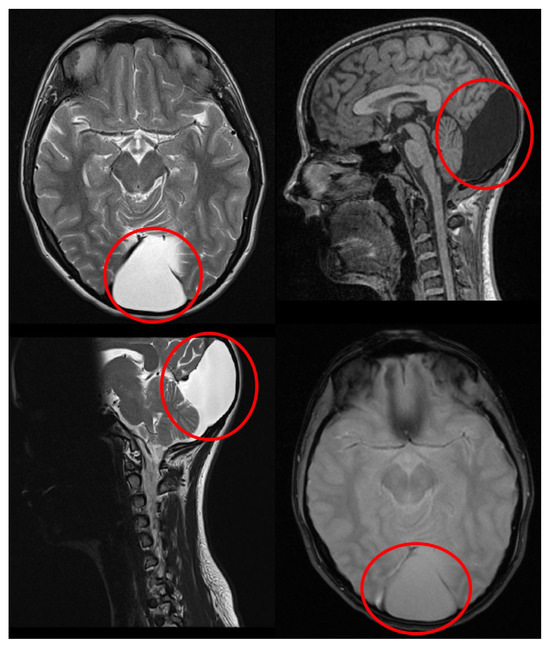

Reversible Cortical Visual Impairment in an Adolescent Due to a Posterior Fossa Arachnoid Cyst: A Case Report

2. Case Report